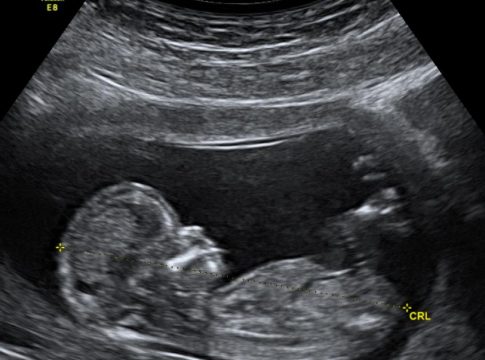

Los recientes avances en la tecnología de secuenciación del ADN y el diagnóstico prenatal han permitido diagnosticar muchas enfermedades genéticas antes del nacimiento. Algunas de estas enfermedades se tratan con terapias de sustitución de proteínas o enzimas después del nacimiento, pero para entonces, algunos de los efectos perjudiciales de la enfermedad se han afianzado. Por lo tanto, la aplicación de terapias mientras el paciente está todavía en el útero tiene el potencial de ser más eficaz para algunas condiciones. El pequeño tamaño del feto permite una dosis terapéutica máxima, y el sistema inmunológico fetal inmaduro puede ser más tolerante a la terapia de reemplazo.

A fin de identificar posibles sistemas de entrega no virales para el ARNm terapéutico, los investigadores crearon una biblioteca de nanopartículas lipídicas, pequeñas partículas de menos de 100 nanómetros de tamaño que entran efectivamente en las células de los receptores fetales de ratones. Cada formulación de nanopartículas lipídicas se utilizó para encapsular el ARNm, que se administró a fetos de ratones.

Los investigadores descubrieron que varias de las nanopartículas lipídicas permitían la entrega de ARNm funcional a los hígados fetales y que algunas de esas nanopartículas lipídicas también entregaban ARNm a los pulmones e intestinos fetales. También evaluaron la toxicidad de las nanopartículas lipídicas y descubrieron que eran tan seguras o más seguras que las formulaciones existentes.